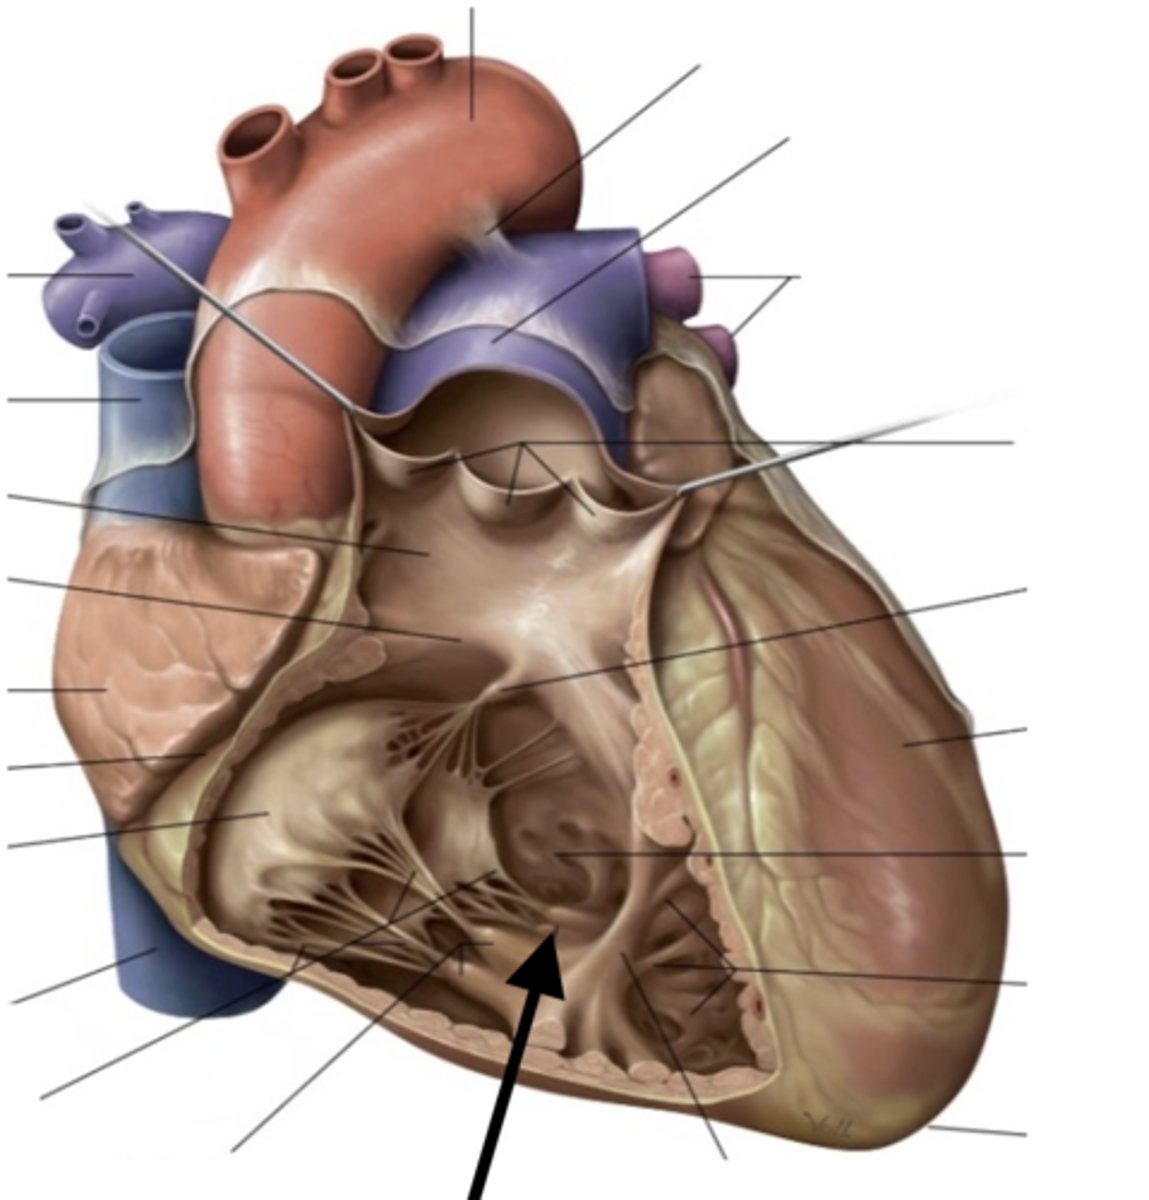

left atrioventricular orifice

opening between left atrium and left ventricle

mitral valve

valve between the left atrium and the left ventricle; bicuspid valve

shaped like a bishops hat

aortic vestibule

the narrowing "outflow part" of the ventricle leading to the ascending aorta

opening of ascending aorta

probe going through the aorta

aortic valve

all three cusps make up the...

interventricular septum

separates ventricles

muscular part of interventricular septum

Most of the septum is thick. This is the thick part

membranous part of the interventricular septum

thin upper-most part of the septum

trabeculae carneae

ridges of cardiac muscle

papillary muscles (3)

they tug at your heart strings

tendinous cords

heart strings